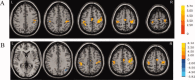

Parkinson's disease (PD) patients have difficulty in initiating movements. Previous studies have suggested that the abnormal brain activity may happen not only during performance of self-initiated movements but also in the before movement (baseline or resting) state. In the current study, we investigated the functional connectivity of brain networks in the resting state in PD. We chose the rostral supplementary motor area (pre-SMA) and bilateral primary motor cortex (M1) as "seed" regions, because the pre-SMA is important in motor preparation, whereas the M1 is critical in motor execution. FMRIs were acquired in 18 patients and 18 matched controls. We found that in the resting state, the pattern of connectivity with both the pre-SMA or the M1 was changed in PD. Connectivity with the pre-SMA in patients with PD compared to normal subjects was increased connectivity to the right M1 and decreased to the left putamen, right insula, right premotor cortex, and left inferior parietal lobule. We only found stronger connectivity in the M1 with its own local region in patients with PD compared to controls. Our findings demonstrate that the interactions of brain networks are abnormal in PD in the resting state. There are more connectivity changes of networks related to motor preparation and initiation than to networks of motor execution in PD. We postulate that these disrupted connections indicate a lack of readiness for movement and may be partly responsible for difficulty in initiating movements in PD.